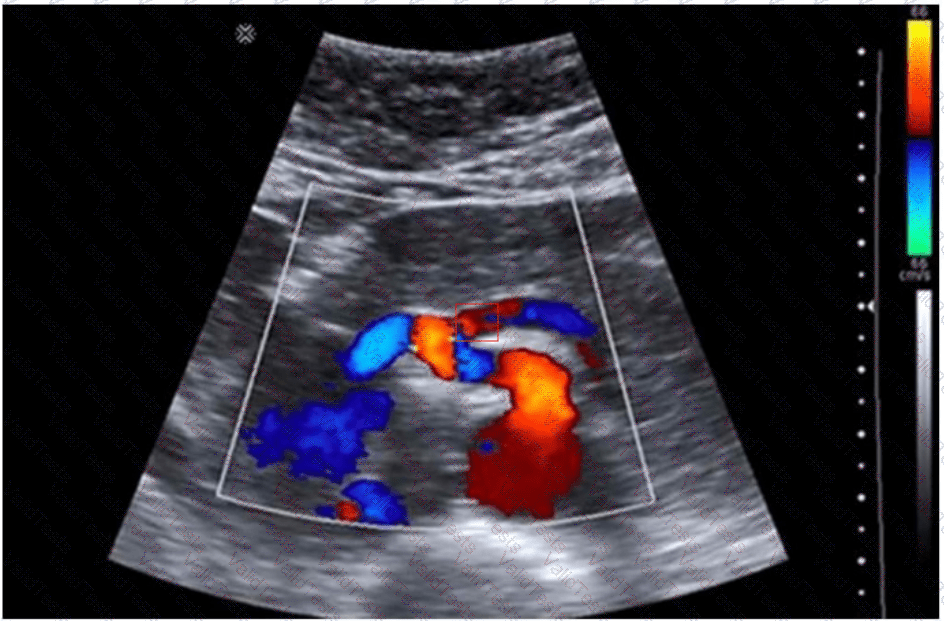

The image provided is a color Doppler ultrasound scan of the abdominal aorta and its major branches. In the center of the image, just anterior to the aorta, we see the superior mesenteric artery (SMA) arising in the sagittal plane. This is the critical area for Doppler sampling in a patient with symptoms suggestive of mesenteric ischemia.

Peak systolic velocity (PSV): >275 cm/s suggests ≥70% SMA stenosis

Sampling must be performed at the narrowest origin point (as shown in the image)

The site shown in the image is ideal for measuring PSV and evaluating for stenosis or extrinsic compression.